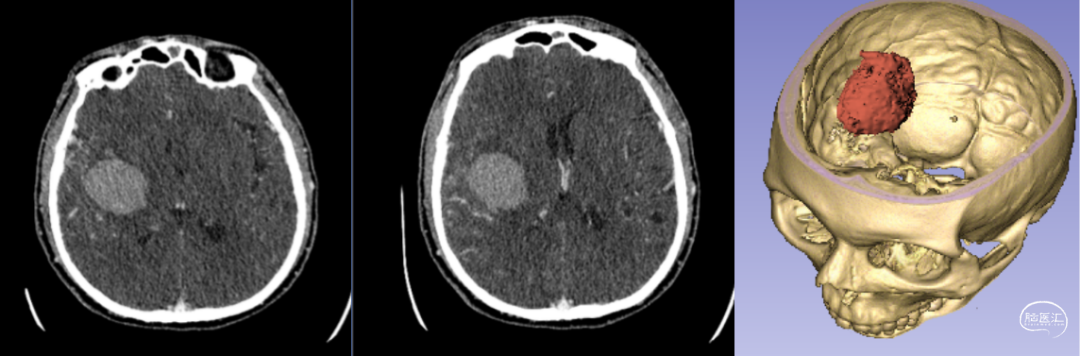

7.1 3D打印技術(shù)定位下腦內(nèi)血腫穿刺術(shù)

3D打印可以制作個(gè)性化的手術(shù)導(dǎo)板。在神經(jīng)外科手術(shù)中,手術(shù)導(dǎo)板可以幫助醫(yī)生更準(zhǔn)確地進(jìn)行鉆孔、切割等操作。在顱骨鉆孔時(shí),定制的3D打印手術(shù)導(dǎo)板能夠確保鉆頭準(zhǔn)確地到達(dá)病變部位,提高手術(shù)的精準(zhǔn)性。

新疆醫(yī)科大學(xué)第一附屬醫(yī)院神經(jīng)外科中心已成功將該技術(shù)應(yīng)用于多例腦卒中患者的治療。以一例典型病例為例:[14]

- 患者情況:52歲女性,因“右側(cè)肢體無(wú)力1天”就診,入院時(shí)呈淺昏迷狀態(tài),雙側(cè)瞳孔等大等圓(直徑約3.5mm),對(duì)光反射遲鈍,右側(cè)肢體肌力為0級(jí)。

- 手術(shù)過(guò)程:基于術(shù)前影像數(shù)據(jù),團(tuán)隊(duì)利用3D打印技術(shù)設(shè)計(jì)并制作個(gè)性化手術(shù)導(dǎo)板,精準(zhǔn)定位血腫位置后實(shí)施穿刺引流。術(shù)后復(fù)查頭部CT顯示,引流管準(zhǔn)確位于血腫腔內(nèi),血腫清除效果良好。